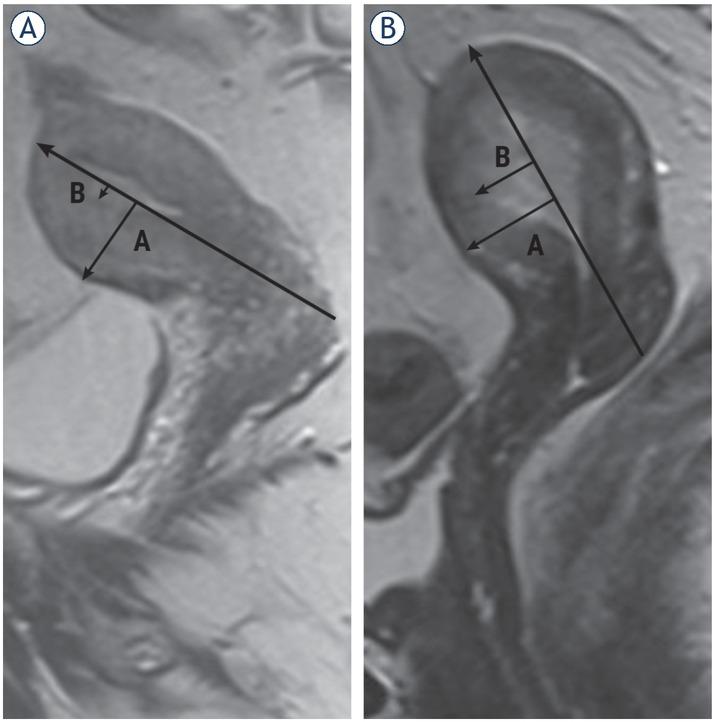

In order to measure the depth of MI on MRI, the line must be drawn along the expected inner edge of the myometrium (corresponding to the endomyometric junctional zone) on axial oblique plane obtained perpendicular to the endometrium; then, two measures should be taken: one represents the thickness of the entire myometrium; the second is measuring the maximum range of tumor within the myometrium. The ratio of these measures represents the percentage of MI. The ratio of the thickness of the tumor from the uterine cavity to the outer border and the total thickness of the

myometrial wall on the side on which the tumor is located was calculated (Figure 3).

Assessment of myometrial invasion in patients with MRI, sagittal T2-weighted. Stage IA endometrial cancer in a 68-year-old postmenopausal woman, correctly diagnosed by TVUS and MRI. Arrow shows blurring of the junctional zone and the infiltration of superficial muscle (20%) (A). Stage IB endometrial cancer in a 58-year-old postmenopausal woman, correctly diagnosed by TVUS and MRI. Arrows refers to deep myometrial infiltration (60%) (B).